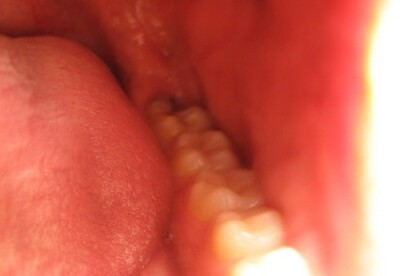

Seguir un tratamiento para encías sangrantes puede ser muy útil, si antes se conocen las causas de esta enfermedad periodontal, la que es conocida como gingivitis, la que se caracteriza por ser una inflamación e infección que se encarga de destruir los tejidos de soporte de los dientes. Esto se produce por los depósitos a largo plazo de la placa en los dientes, material pegajoso compuesto de bacterias y residuos de alimentos que se acumulan en las zonas expuestas de los dientes, provocando el sangramiento y siendo además una de las causantes de las caries dentales.

Las causas del sangramiento en las encías, son diversas como una mala higiene bucal, diabetes no controlada, dientes mal alineados y ciertas infecciones; donde una mala alimentación y problemas digestivos también pueden ocasionar esto, donde el cepillarse muy fuerte, tener bajas defensa y tener un déficit de vitaminas también son factores que también pueden influir en la aparición de sangre en las encías, lo que se manifiesta generalmente al cepillar los dientes.